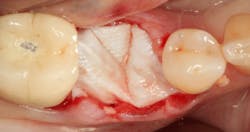

After the photo was taken to demonstrate the membrane placement, a periosteal elevator was used to further push the membrane under the lingual flap so that it draped intimately over the graft. The partial-thickness flap preparation made during initial incisions allowed for coronal positioning for tension-free primary closure. A CV-5 horizontal mattress suture was used to bring the buccal and lingual flaps together, and closure was completed with interrupted sutures.

Stage II uncovering was performed five months following the initial surgery. A crestal incision was made toward the lingual ridge to split the keratinized gingiva, as that is where the keratinized gingiva had settled following surgery due to the coronal advancement of the buccal flap to obtain primary closure. The keratinized gingiva was buccally positioned, and a healing abutment was placed. The tissue was sutured with 4.0 chromic gut. This allowed the attached gingiva to heal on the buccal portion of the healing abutment and thus remain on the buccal portion of the final restoration. Final impressions were taken two weeks later, and the restoration was delivered thereafter.